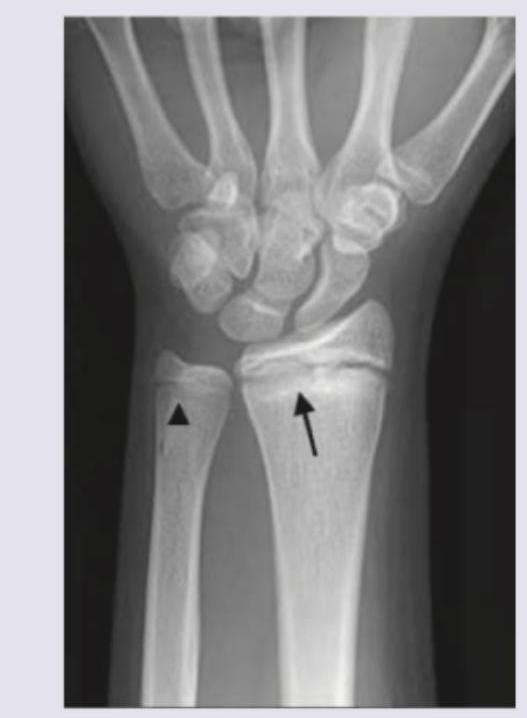

What is the predicted bone age from the wrist radiograph given below? (AIMMS May 2016)

Explanation: ***<17.5 years*** - The image shows that the **growth plates (epiphyseal lines)** of both the **radius (arrow)** and **ulna (arrowhead)** are still open but are clearly nearing fusion. This appearance generally indicates a bone age of **less than 17.5 years**. - A fully fused epiphysis, signifying complete skeletal maturity, typically occurs around 17.5 years in females and slightly later in males, but here the **growth plates are still visible**. *18-19 years* - By 18-19 years, the **epiphyseal growth plates** of the distal radius and ulna are typically **completely fused**, indicating full skeletal maturity. The radiograph clearly shows a visible growth plate. - This age range would show **no distinct radiolucent line** between the epiphysis and metaphysis. *20-22 years* - This age range represents a fully skeletally mature individual, where **all growth plates** throughout the body, including the wrist, would be **completely closed and obliterated**. - The presence of **open growth plates** in the image rules out this age estimate. *<12 years* - At an age of less than 12 years, the **growth plates would be much wider and more distinct**, with less evidence of imminent fusion. - The carpal bones would also typically be **less ossified** and have a more immature appearance compared to what is shown.